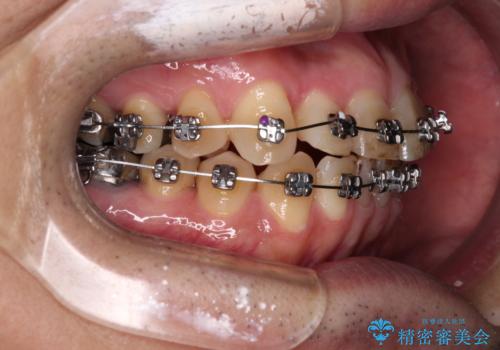

- 近医にてブリッジ治療を行った歯が痛くてたまらないとのことで来院された患者様です。

診察を行ったところ、奥の土台になっている歯は神経組織が失活しており、根尖部に病変があり、そこが原因で痛みを生じている状態でした。

根管治療を行うためにブリッジを除去したところ、むし歯が歯肉の奥深くにあまで及んでいたため、歯周外科処置によりむし歯が歯肉縁より浅い位置へと改善することとしました。

ここまでの治療を提案したところで、折角なのでしっかり治療を行いたいとのことで、前歯のデコボコやクロスバイトを改善するための矯正治療を行うこととしました。

まずは奥歯の痛みを改善し、その後矯正治療を行い、最後にオールセラミックブリッジによる補綴治療を行うこととしました。

むし歯をきっかけに矯正治療を行うこととなりましたが、学生の頃から気になっていた歯列を改善することができ、患者様には大変満足していただけました。